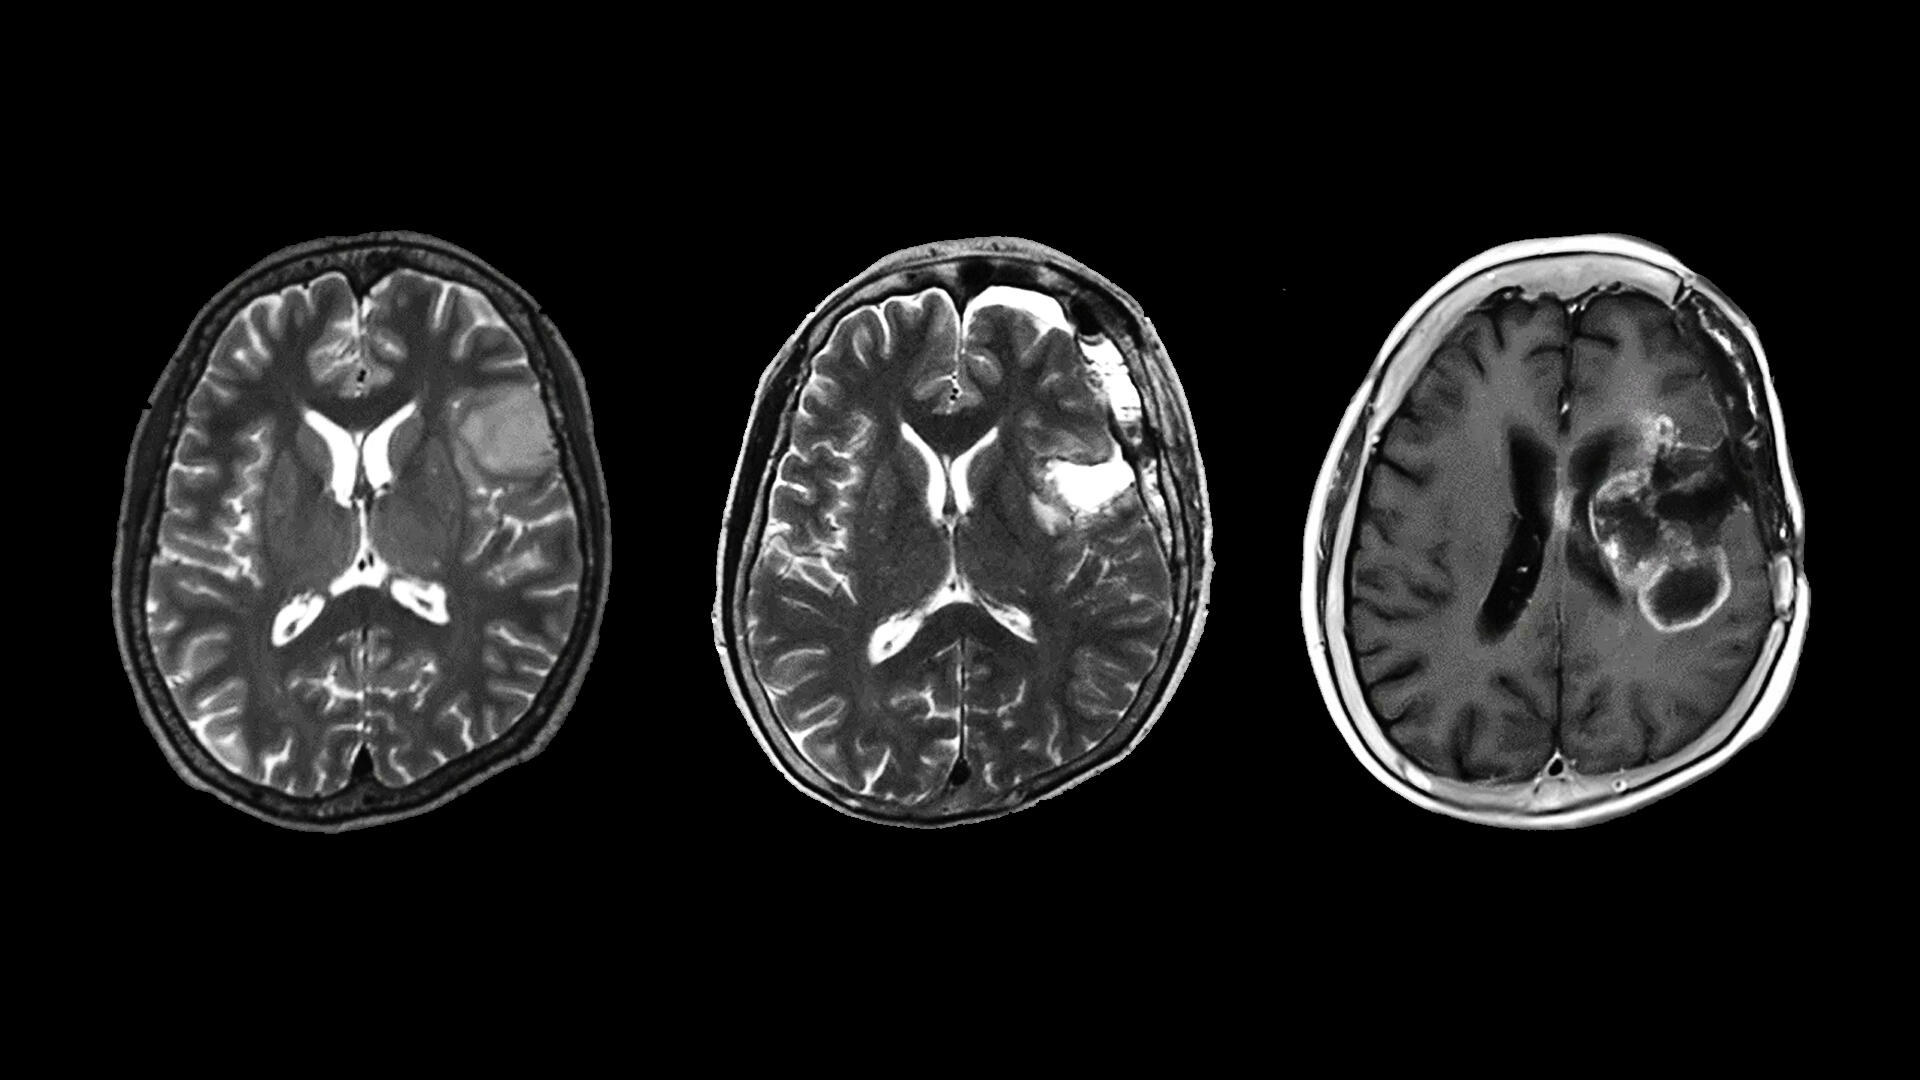

They initially created rat models with Brca2 mutations that mimic human BRCA2 pathological variants, using a gene-editing technology. These mutant rats spontaneously developed malignant tumors at a rate of 36.8%, which is significantly higher than the 5.3% observed in wild-type rats. This result confirmed that the model accurately reflects human hereditary cancer risk.

The researchers then induced oxidative stress in the Brca2 mutant rats by administering ferric nitrilotriacetate (Fe-NTA) to their renal tubules. They used Fe-NTA, a form of iron, in this experiment, because oxidative stress caused by iron overload is reported to be highly associated with cancer development. However, no differences were found in tumor incidence, progression speed or malignancy grade between wild-type and Brca2-mutant rats. Then, they investigated why iron-dependent oxidative stress canceled the cancer-promoting effect of the BRCA2mutation.

However, three weeks after starting Fe-NTA administration, the researchers observed the opposite effect. In the Brca2 mutant rats, the accumulation of catalytic iron damaged mitochondria and led to an increase in lipid peroxidation. As a result, ferroptosis was activated, which surprisingly contributed to the elimination of cells with the potential to become cancerous. These results suggest that ferroptosis counteracted the genomic instability caused by BRCA2 deficiency, acting instead as a tumor suppressor.

The experiments revealed that, rather than promoting the development of cancer, iron-induced oxidative stress inhibited it in Brca2 mutant rats. This is the first experimental evidence contradicting the hypothesis that iron-induced oxidative stress promotes cancer development in individuals with BRCA2 pathological variants.